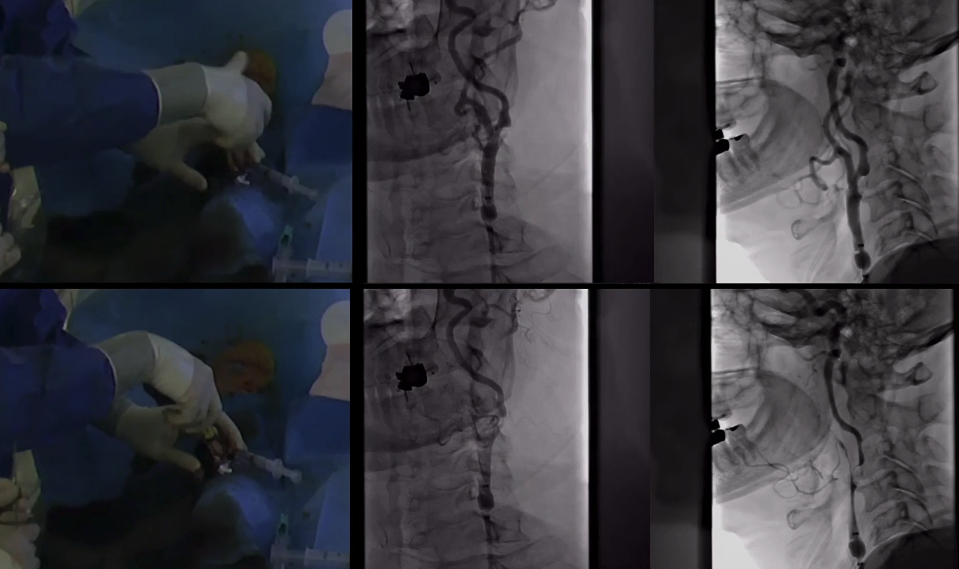

演示视频

步骤解析

颈动脉分叉部狭窄病变

路图引导下,BGC置于颈总动脉,病变近端充盈球囊

球囊充盈后,手推造影,造影剂滞留能进一步明确狭窄病变特征。开放阀门(stopcock),可见造影剂回流,提示反向血流建立

路图引导下,导丝通过狭窄

远端保护伞到位

支架释放完毕

球囊后扩

球扩后造影

保护伞回收

最终成形效果

颅内血流明显改善